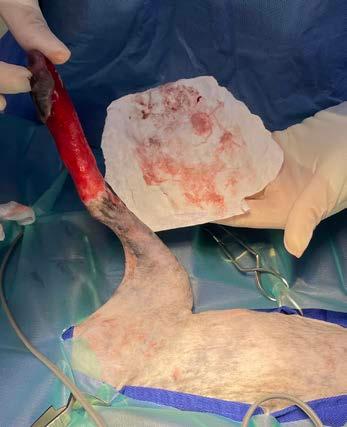

Se realiza la necropsia en la que se observa el corazón dentro del saco pericárdico con abundante líquido pericárdico. Se observa una gran masa redondeada de 7 x 5 x 3 cm en la base de la aorta, de consistencia firme, vascularizada, la cual al corte presenta vascularización y cavitaciones, áreas de hematoma y áreas de tejido graso y tejido fibroso. Se observa engrosamiento y degeneración de ambas válvulas atrioventriculares y, además, presencia de un nódulo en la válvula tricúspide de aspecto liso, color beige, no vascularizado de 1,5 cm. Se realizó en la toma y envío de muestras de las lesiones observadas en la base de corazón y tricúspide (Figs. 7, 8, 9 y 10). El análisis histopatológico de ambas lesiones confirma la sospecha diagnóstica de quemodectoma, siendo el nódulo tricúspide metástasis de la neoplasia principal en la base aórtica (Fig. 11), ya

Figura 7. Imagen de corazón evidenciando masa en base aórtica (flecha). Figura 8. Detalle de masa adherida a aorta. Masa esponjosa, cavitada, vascularizada, con áreas de necrosis y tejido adiposo. Figura 9. Detalle de masa tricúspide (flecha). Visión desde aurícula derecha. Figura 10. Detalle de masa tricúspide (flecha) adherida a las valvas. Vista gracias a la apertura completa del ventrículo derecho.

Figura 11. Vista histopatológica de tumor neuroendocrino: Se observa una proliferación de células poligonales formando nidos y paquetes y también áreas de empalizada alrededor de pequeños vasos sanguíneos. Las células muestran bordes indefinidos, citoplasma escaso a moderado eosinófilo finamente granular, núcleo redondo, cromatina granular y nucléolo variablemente presente, pequeño, redondo y basófilo. La anisocitosis y anisocariosis son moderadas.

que al examen microscópico en ambas localizaciones se observaron células de bordes indefinidos, citoplasma escaso a moderado eosinófilo finamente granular, núcleo redondo, cromatina granular y nucléolo variablemente presente, pequeño, redondo y basófilo. También se observó anisocitosis y anisocariosis moderadas. Se reconocieron mitosis en 10 campos de 40X a través de la autólisis en la muestra. Se diagnosticó así en la muestra de aorta y tejido adiposo de la base cardíaca un carcinoma neuroendocrino, consistente con quemodectoma, con invasión intravascular. En la muestra de la válvula tricúspide y miocardio de la pared ventricular derecha se diagnosticó metástasis valvular miocárdica de carcinoma neuroendocrino y degeneración mixomatosa de la válvula tricúspide, marcada, crónica y difusa (endocardiosis). Además, la lesión neoplásica en tricúspide presentaba carácter infiltrativo hacia el tejido miocárdico de la pared ventricular derecha y epicardio (Fig. 12).